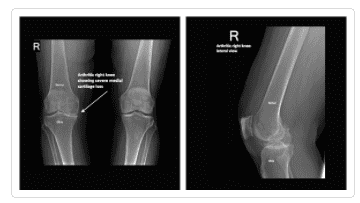

Knee X-ray Gallery

Please visit our knee x-ray gallery to see more images of knees affected by osteoarthritis.